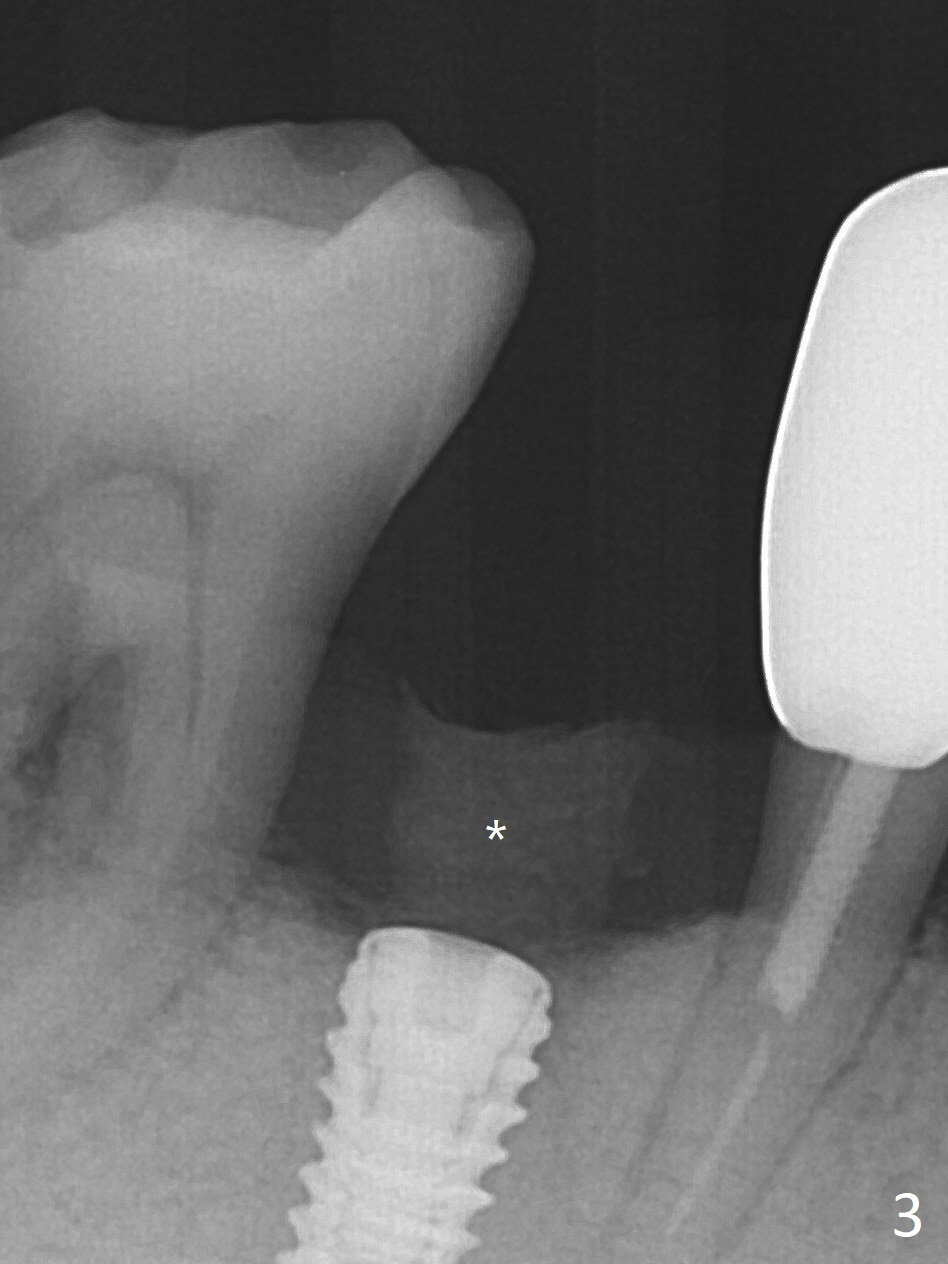

At the time of surgery, there are no 5x10 mm implants in the office for the sites of #14 and 15. Reanalysis of CT shows that there is enough bone for 11.5 mm implants. Before implant placement (Fig.1), there is no perforation of the sinus floor, as shown by probing and nasal blowing test. When a 3.5x11.5 mm implant is placed at #29 in the same appointment, it appears to be supracrestal buccal. Autogenous bone (Fig.2,3 *) is placed in the osteotomy following insertion of a healing screw (S). Periodontal dressing is applied, but it is dislodged after dinner. In fact there is bone coronal to the implant 4.5 months postop (Fig.4), which is confirmed during uncover procedure. There is no abnormality at #14 or 15 4.5 months postop (Fig.5). Impression is taken following extraction of the abnormally shifted opposing tooth #18.